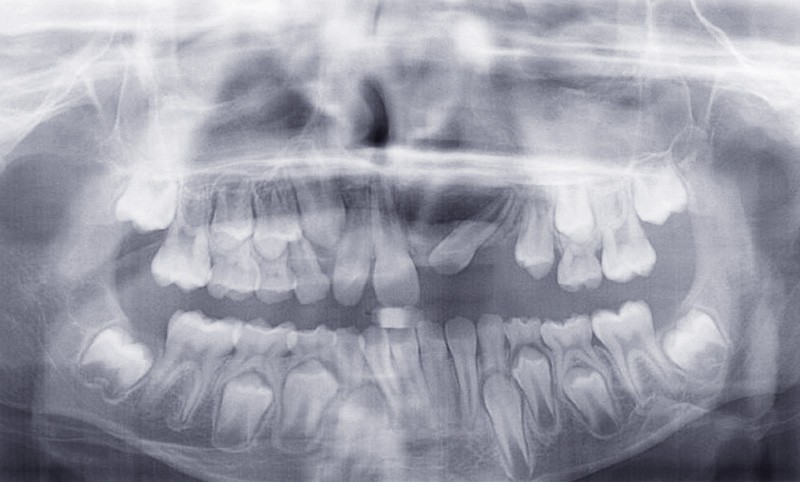

Le jeune Yoan 9 ans est adressé par son chirurgien maxillofacial, suite à l’exérèse d’un kyste bénin du maxillaire, et l’avulsion de 21 et 23 (fig. 1). L’apex de 22 a été soufflé par le kyste. La céphalométrie (fig. 2a et b) et l’examen clinique mettent en évidence une classe II squelettique par rétromandibulie, ainsi qu’une classe II dentaire. Le patient, est particulièrement perturbé par l’intervention qu’il vient de subir, et la coopération s’annonce difficile.

La gestion esthétique immédiate passe par un traitement orthodontique précoce, car la position de 22 (fig. 3) empêche toute restauration provisoire de l’édentement. Au vu du contexte, le choix thérapeutique se portera sur la simplicité, la rapidité, l’esthétique puis la réévaluation sur le long terme.

La 22 doit être remise sur l’arcade et le choix est fait de la mettre en lieu de 21 (fig. 4), puis de la maquiller pour temporiser en attendant l’évolution des autres dents définitives, et éviter le port d’une prothèse amovible transitoire (P.A.T.) tout en ramenant de l’os alvéolaire dans l’espace de 21.